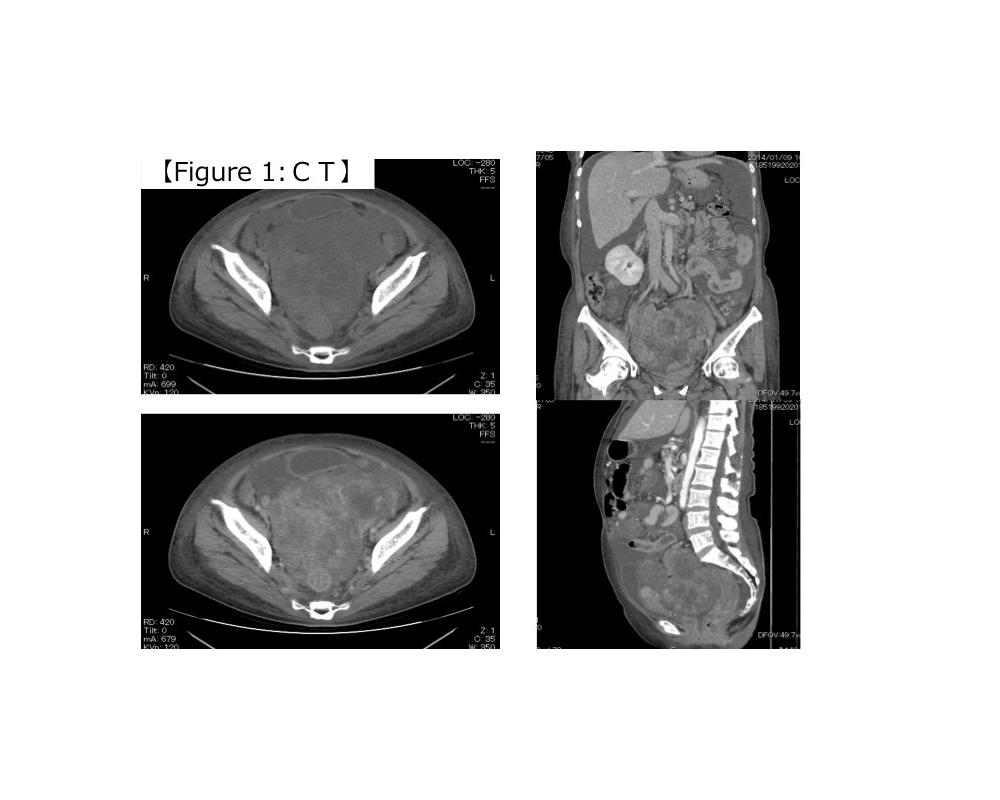

第36回日本臨床細胞学会九州連合会学会(大分)スライドカンファレンス症例4

種別:体腔液

出題:宮崎県立宮崎病院 病理診断科 丸塚 浩助

| 年齢 | 50代後半 | 性別 | 女性 |

|---|---|---|---|

| 採取部位 | 腹水 | 採取方法 | 穿刺 |

| 検体処理法 | 塗抹及びLBC |

臨床所見

<既往歴>

特記なし

<現病歴>

2ヶ月前頃より腹部膨満・下腿浮腫を自覚し、当院産婦人科に紹介受診。MRIにて著明な腹水と骨盤腔内を占める腫瘤が認められ、癌性腹水を伴う卵巣癌との臨床診断で腹水穿刺細胞診が行われた。

化学療法後開腹手術を行ったが、びまん性腹膜播種を認め、腫瘍切除のみ行われた。腫瘍はS状結腸腸間膜に存在し、卵巣・子宮は正常外観であった。

| 正解 | 5.炎症性筋線維芽細胞肉腫 |

▼選択肢及び投票結果

| 1.卵巣漿液性腺癌 | 5件 | (7.8%) | |

| 2.腹膜中皮腫 | 3件 | (4.7%) | |

| 3.消化管間質腫瘍 | 1件 | (1.6%) | |

| 4.未分化大細胞リンパ腫 | 42件 | (65.6%) | |

| 5.炎症性筋線維芽細胞肉腫 | 13件 | (20.3%) | |

| 投票総数 | 64件 | (100%) |